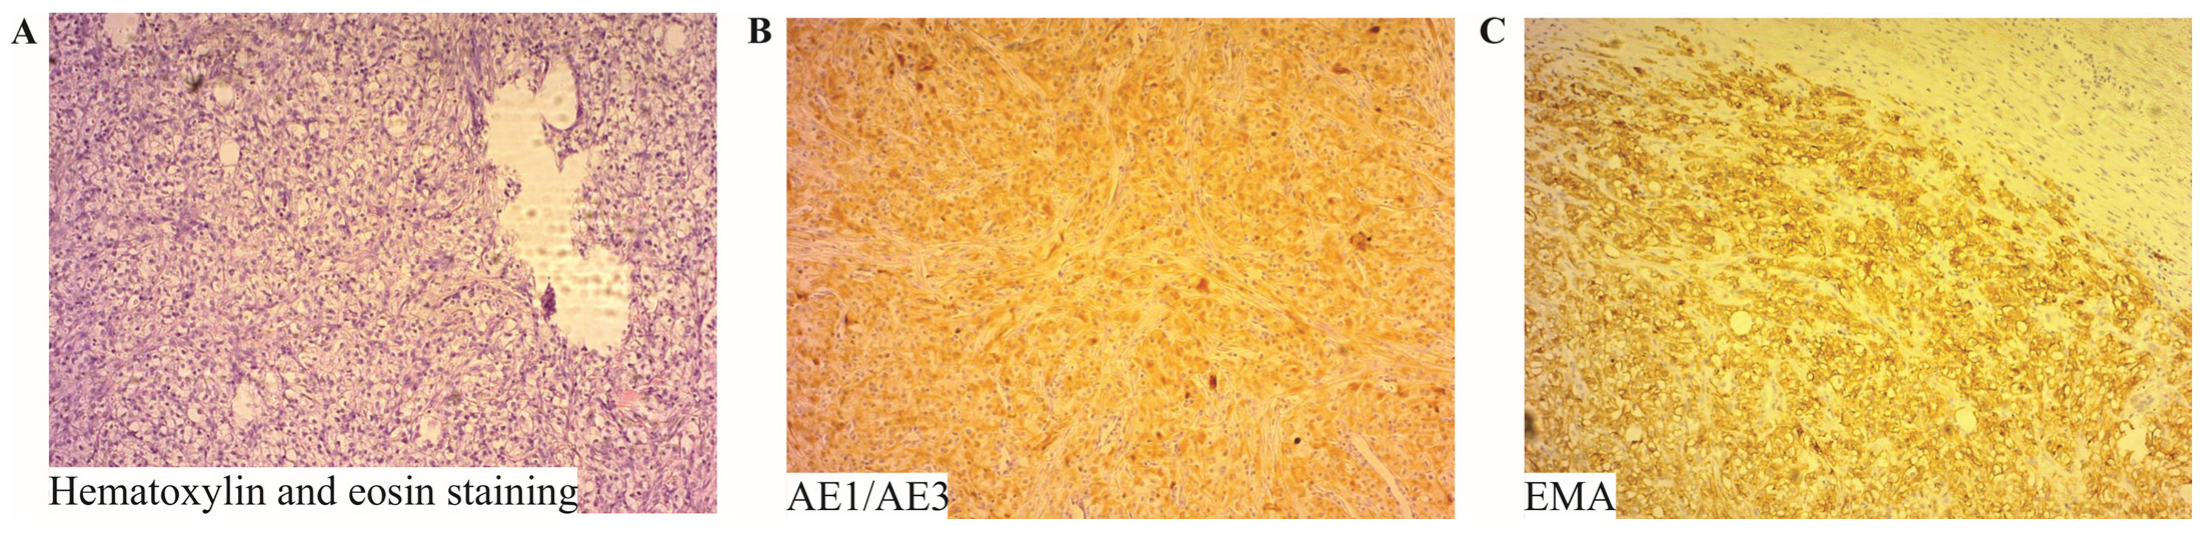

2.5. Histopathological Evaluation of Surgical Specimen

| Importance of Histopathology | Detailed histopathological examination is crucial for confirming the diagnosis of RCC metastasis. |